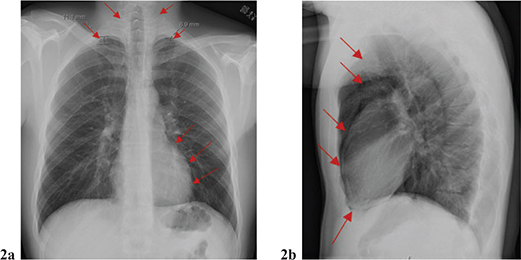

Upon reevaluation of the physical examination, it was found that the subcutaneous emphysema had progressed to the supraclavicular region, and the patient complained of pain in the left shoulder. A subsequent computed tomography of the chest confirmed bilateral pneumothorax, pneumomediastinum with air extending up to the neck, pneumopericardium, and pneumoperitoneum (Figure 2a–f). Additionally, the air was observed dissecting along the major bronchus toward the pericardium (Figure 2f). A small amount of air was noted to have dissected its way up to the neck, right up to the base of the skull (Figure 2a–e). Most air is in the lower throat. After consulting a surgeon and conducting further investigations, it was determined that esophageal perforation was not the cause of the issue.

Fig 2

Figure 2 (a–f) Chest CT: As with the previous chest X-ray, a bilateral pneumothorax was confirmed. Pronounced pneumomediastinum extending up the neck bilaterally. Air (red arrow) has also been dissected along large bronchi and to the pericardium.